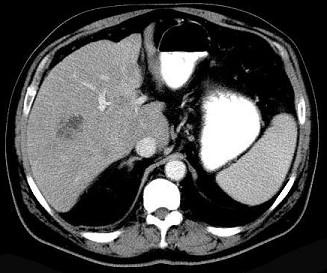

问题 细菌性肝脓肿的最常见致病菌是 ( )

选项 A、粪链球菌、金黄色葡萄球菌和厌氧菌 B、溶血性链球菌、金黄色葡萄球菌和厌氧菌 C、大肠杆菌、粪链球菌和厌氧菌 D、大肠杆菌、金黄色葡萄球菌和厌氧菌 E、大肠杆菌、绿脓杆菌和厌氧菌

答案 D